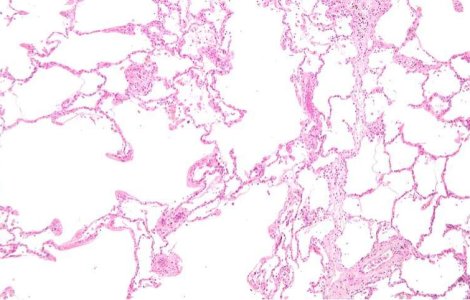

Incredibil 13 May. 2011

Tehnica inovatoare: Au fost descoperite celulele susa care ajuta la regenerarea plamanilor.